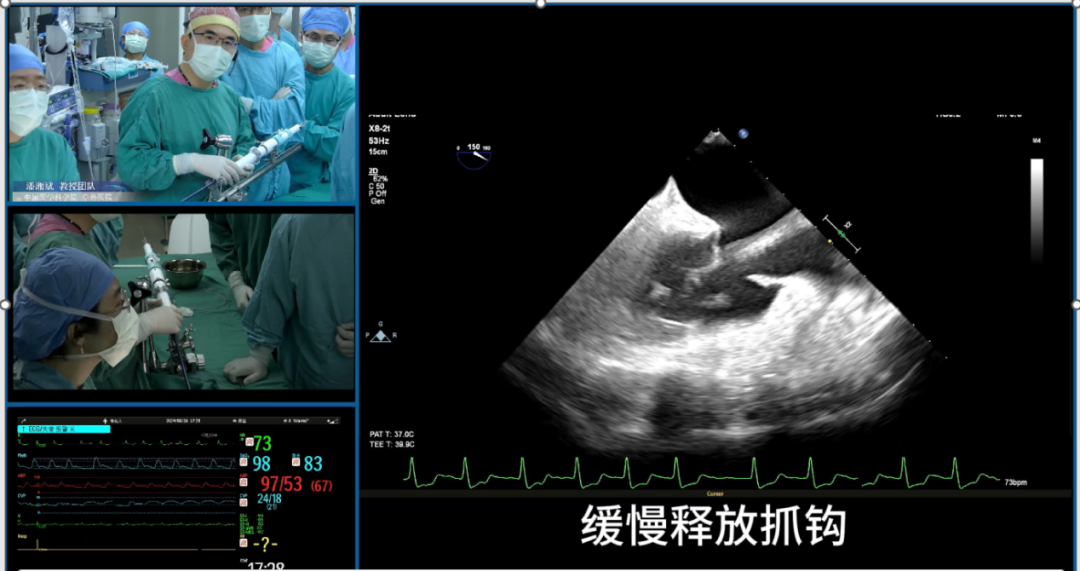

施浩教授介绍了一例成功进行单纯超声引导下经导管三尖瓣置换术的病例,从术前CT评估,术前3D打印体外模拟多方面详细介绍了术前评估流程,并且展示了术中超声过程。

赵广智教授以两例成功进行全超声引导下三尖瓣TEER的病例为例,详细介绍了该技术的术中操作步骤,提供了超声引导三尖瓣TEER的技巧和建议,包括探头操作和多级成像。